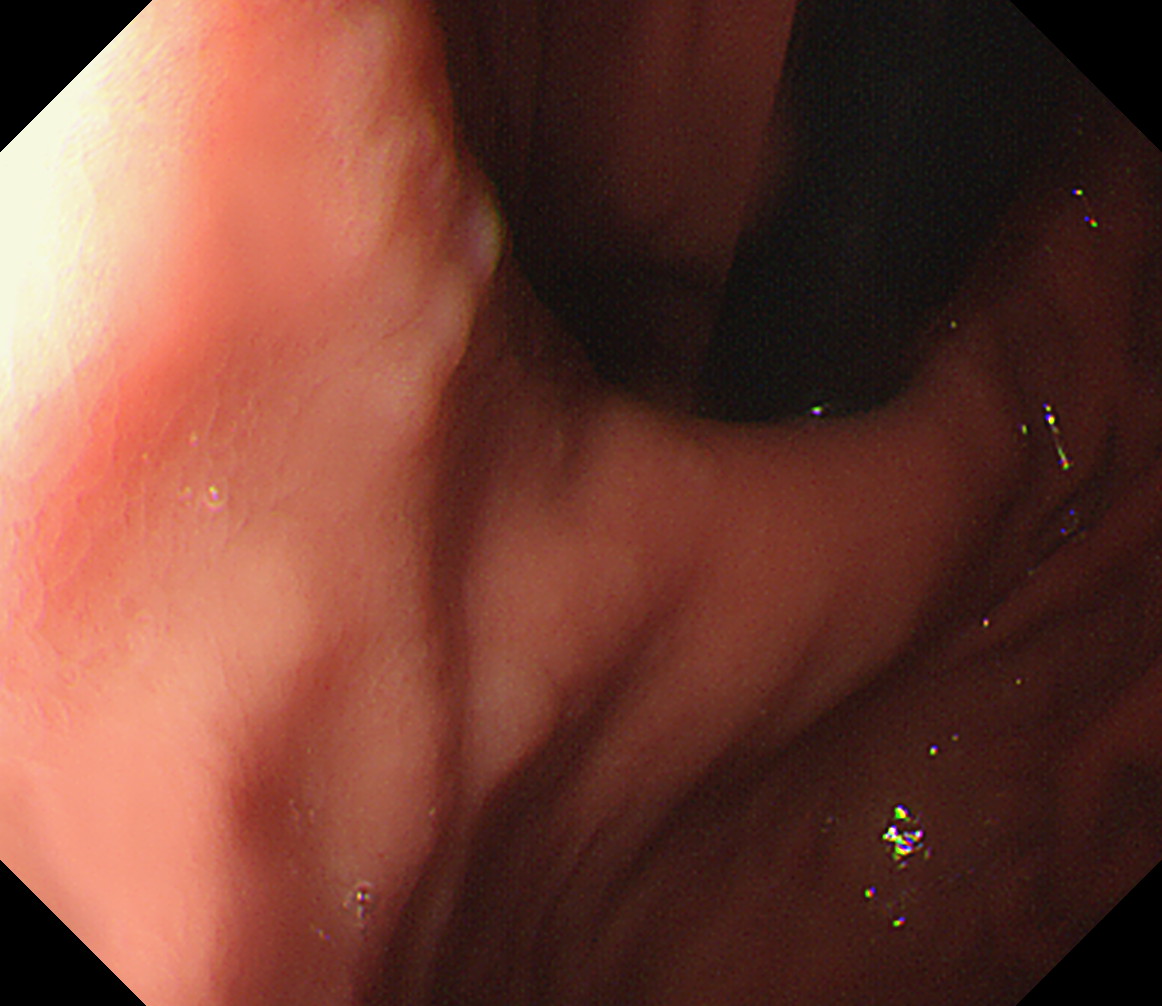

11 胃角部後壁 [見下ろし]になります 中部食道

12 胃角部小弯 [J反転]見上げになります 胃角部後壁

13 胃角部前壁 再度、[見下ろし]になります 胃角部前壁